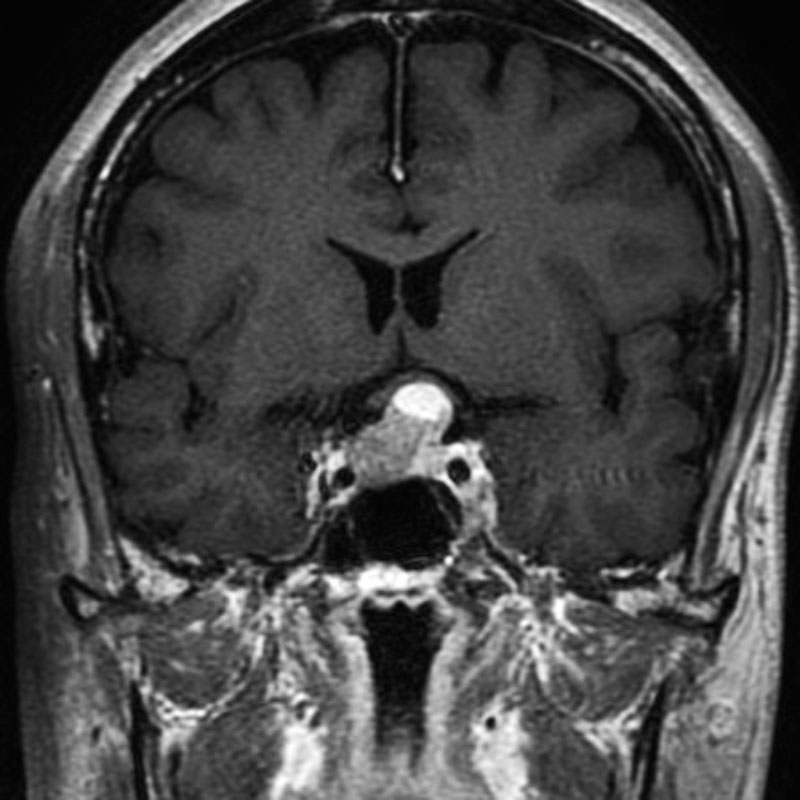

412

'23年5月

20代

小脳血管芽腫

頭蓋内腫瘍摘出術

No.’23_46 手術前1

No.’23_46 手術前2

No.’23_46 摘出 前

No.’23_46  摘出 中

No.’23_46 摘出 後